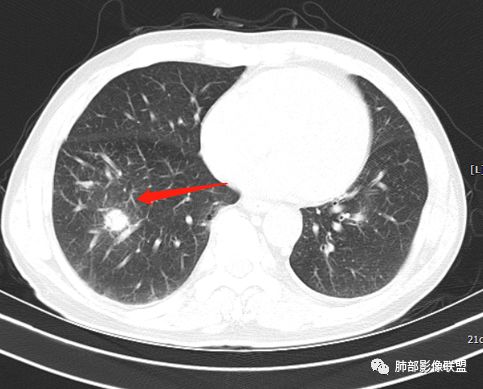

膈面上还有一个结节

左肺上叶病灶长轴与支气管走形一致,提示沿支气管分布病变,倾向于炎性,大家可能怀疑这个病例是来源于胸膜下为主的,胸膜下来源首先整体是来源于胸膜下,与胸膜下之间没有间隙,而这例与胸膜下有间隙。而且这个病变是沿支气管朝外蔓延的,而胸膜下来源的是朝内蔓延的,唯一给我们错觉的是靠近纵隔胸膜这个地方有问题。但是靠近纵隔胸膜这个位置实变不是靠近胸膜实变,它边缘收缩的,没有膨隆的迹象。我们看到里面支气管直达远端稍扩张,是以中央间质为主、小叶间隔朝外蔓延,有间质也有实质病变,走向是沿中央间质方向走的,我个人倾向炎性病变。    问题是右下叶病灶怎么解释?右隔上、右肺门各有一个结节。这个病人有急性咳嗽、胸痛的病史,还有糖尿病病史,周围渗出比较明显,应该警惕炎性病变,要警惕克雷伯杆菌、结核、金葡菌霉菌,因为糖尿病人经常好发这些病菌感染。那么右下叶病变怎么考虑?能不能一元论?    左肺病灶是一个急性渗出为主的病变,一个急性感染的迹象;右肺下叶背段结节,没有看到支气管,增强图支气管壁增厚,局部小结节,呈分叶状,支气管堵塞,没有粘液栓样指套样改变,但是里面有强化,我倾向于癌,其次待排结核。我还是倾向于癌的可能性,恶性可能性大一些,可惜我看不到支气管腔内。还考虑有没有淀粉样变性的问题,弥漫钙化灶最常见的一个是结核,另一个是淀粉样变性。叶段支气管壁有弥漫增厚的迹象。所以淀粉样变性跟结核都要考虑。

1.右肺下叶支气管壁增厚,后壁为主,且显示壁外结节,未见异常强化。这样的结节和蔓延方式一般会高度怀疑气道来源的恶性肿瘤,如鳞癌、粘液表皮样癌、腺样囊性癌等。可惜没有相应病理学资料支持。

右肺下叶近膈面球形病灶缺乏恶性病灶特点,没有分叶、毛刺、牵拉等,应当符合炎性。